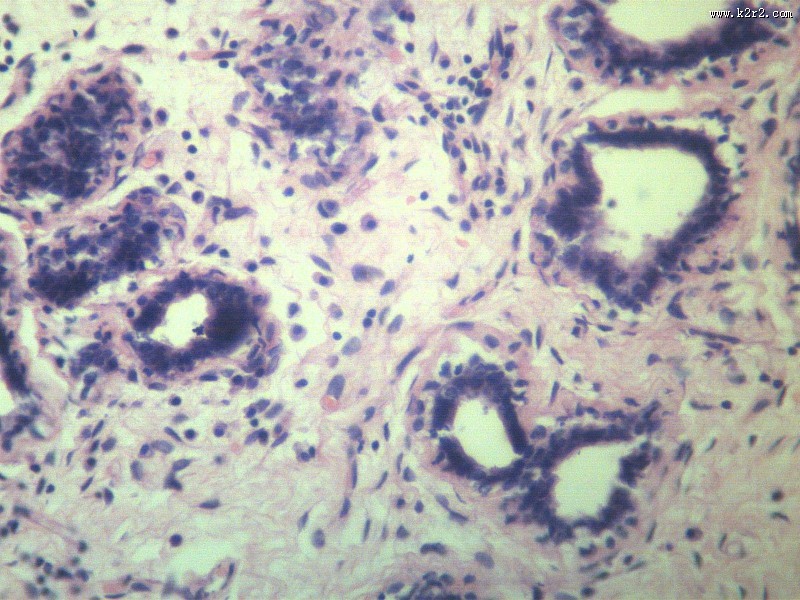

fibroadenoma of breast

乳腺纤维腺瘤

肿瘤显微切片